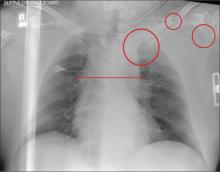

A 57-year-old man is brought to your facility as a trauma code. He was riding a motorcycle on the highway, traveling approximately 45 to 50 mph, when the car in front of him abruptly stopped. He hit the car and was thrown from his bike. He believes he briefly lost consciousness but recalls emergency personnel tending to him. On arrival, he is awake and alert, complaining of pain in his neck, left arm, and left lower leg. Medical history is significant for borderline hypertension and a previous accident that resulted in an emergency laparotomy. Primary survey reveals stable vital signs: blood pressure of 157/100 mm Hg; heart rate, 110 beats/min; respiratory rate, 20 breaths/min; and O2 saturation, 98% with supplemental oxygen. Pupils are equal and reactive; there are slightly decreased breath sounds on the left side. Abdominal exam appears benign. There is decreased mobility and pain in the patient’s left upper and left lower extremities, although no obvious deformity is noted. Preliminary chest radiograph is obtained before the patient is sent for CT. What is your impression?

Several findings are evident from this radiograph. First, the quality is slightly diminished due to the patient’s size and artifact from the backboard. The patient’s mediastinum is somewhat widened, which is concerning for possible occult chest/vascular injury. There is some haziness within the left apical region suggestive of a hemothorax; no definite pneumothorax is seen. The left clavicle is fractured and displaced, and the left scapula is fractured as well.